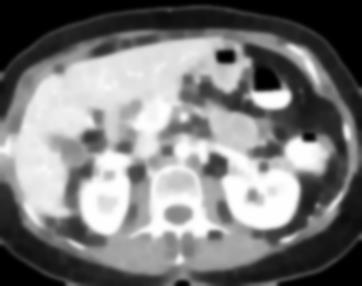

Due to the constraints of the imaging device and high cost in operation time, computer tomography (CT) scans are usually acquired with low intra-slice resolution. Improving the intra-slice resolution is beneficial to the disease diagnosis for both human experts and computer-aided systems. To this end, this paper builds a novel medical slice synthesis to increase the between-slice resolution. Considering that the ground-truth intermediate medical slices are always absent in clinical practice, we introduce the incremental cross-view mutual distillation strategy to accomplish this task in the self-supervised learning manner. Specifically, we model this problem from three different views: slice-wise interpolation from axial view and pixel-wise interpolation from coronal and sagittal views. Under this circumstance, the models learned from different views can distill valuable knowledge to guide the learning processes of each other. We can repeat this process to make the models synthesize intermediate slice data with increasing inter-slice resolution. To demonstrate the effectiveness of the proposed approach, we conduct comprehensive experiments on a large-scale CT dataset. Quantitative and qualitative comparison results show that our method outperforms state-of-the-art algorithms by clear margins.